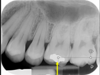

what is this superimposition?

mental foramen